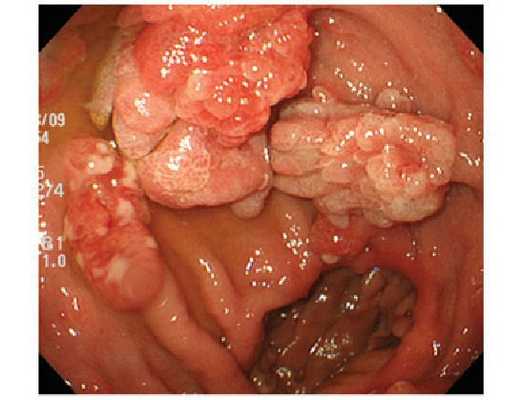

- По форме:

- на толстой или тонкой ножке;

- ровные и гладкие;

- с неровной и бугристой поверхностью, такие полипы похожи на гроздь винограда [7][10] .

Полипы различают по морфологической структуре: железистые, железисто-ворсинчатые и ворсинчатые, гиперпластические, кистозно-гранулирующиеся (ювенильные), фиброзные. Кроме того, выделяют псевдополипоз - разрастания слизистой оболочки по типу полипов при хроническом воспалении. Клинический диагноз так же включает информацию о наличии или отсутствии малигнизации (озлокачествления).